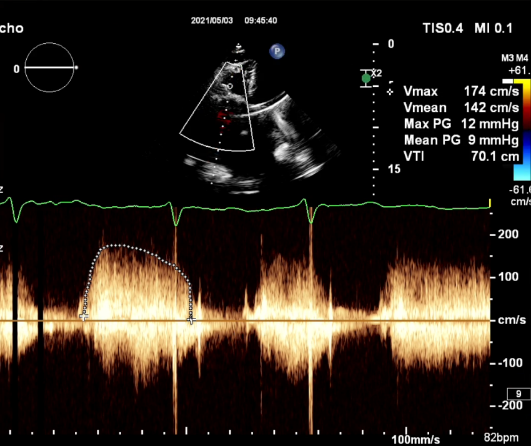

三尖瓣术前平均压差9mmHg

患者为60岁老年女性,18年前因心脏瓣膜病行三尖瓣生物瓣和二尖瓣机械瓣瓣膜置换术,术后恢复顺利;至2年前再次出现无明显诱因的活动后气促等症状,超声结果显示,三尖瓣生物瓣再狭窄,瓣叶增厚,部分交界粘连,开放受限但闭合尚可;二尖瓣机械瓣功能正常,主动脉瓣轻度狭窄伴轻度反流。LVEF为67%,心功能良好,三尖瓣生物瓣平均跨瓣压差10 mmHg。双房明显扩大,肺动脉和冠状静脉窦增宽,右室收缩功能减低。